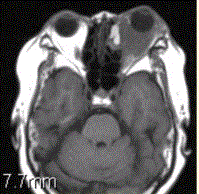

问题 患者女,64岁,左眼突出5年余。查体左眼球前突6mm,眼球运动自如,眼底无异常,下睑扪及边界不清、质软的肿块,视力正常,MR表现如下图。 关于炎性假瘤与眼型Grave病的区别,正确的表述是

选项 A.可发生于甲状腺功能正常者 B.只发生于甲状腺功能正常者 C.突眼程度可与临床表现、实验室检查结果不相符 D.后者为无痛性突眼 E.后者病理改变为眼外肌水肿 F.前者肌腱、肌腹同时增粗,后者肌腹增粗

答案 ACDEF